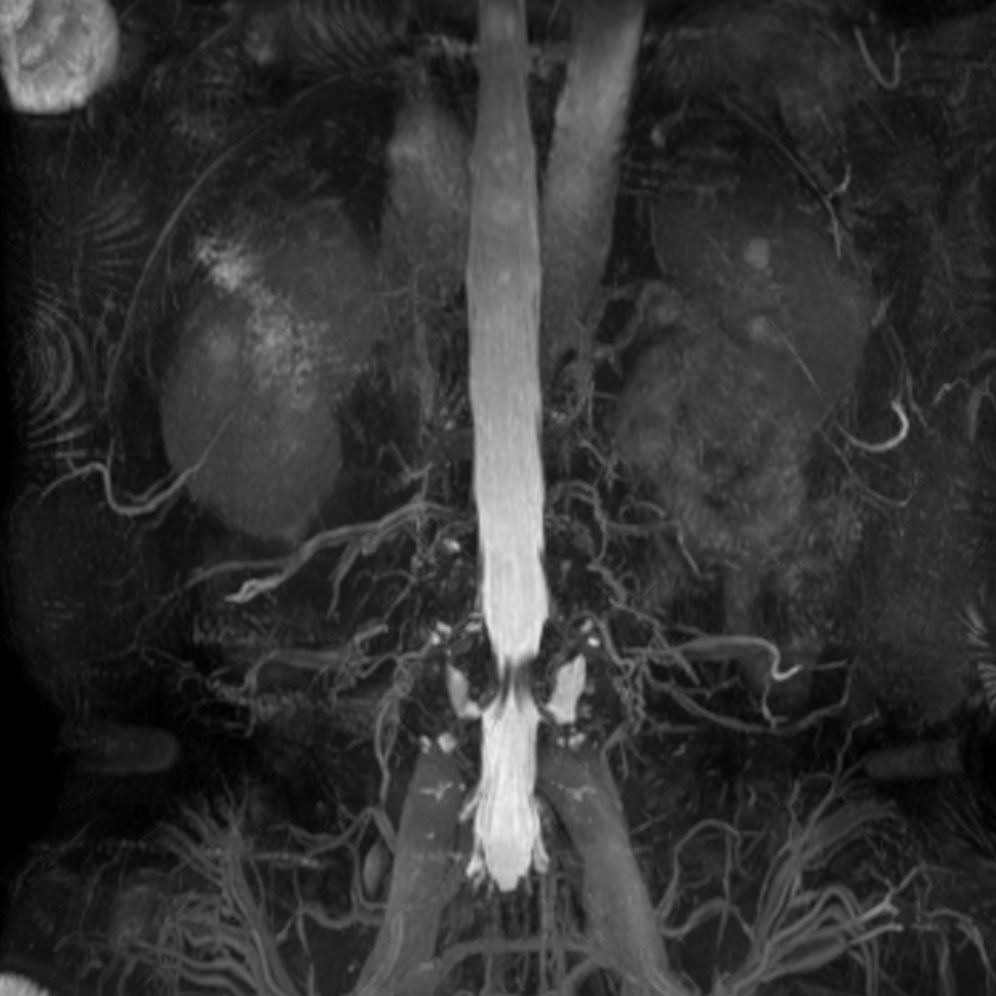

Lumbar Spine disc herniation

Patient with a lumbar spine disc herniation.